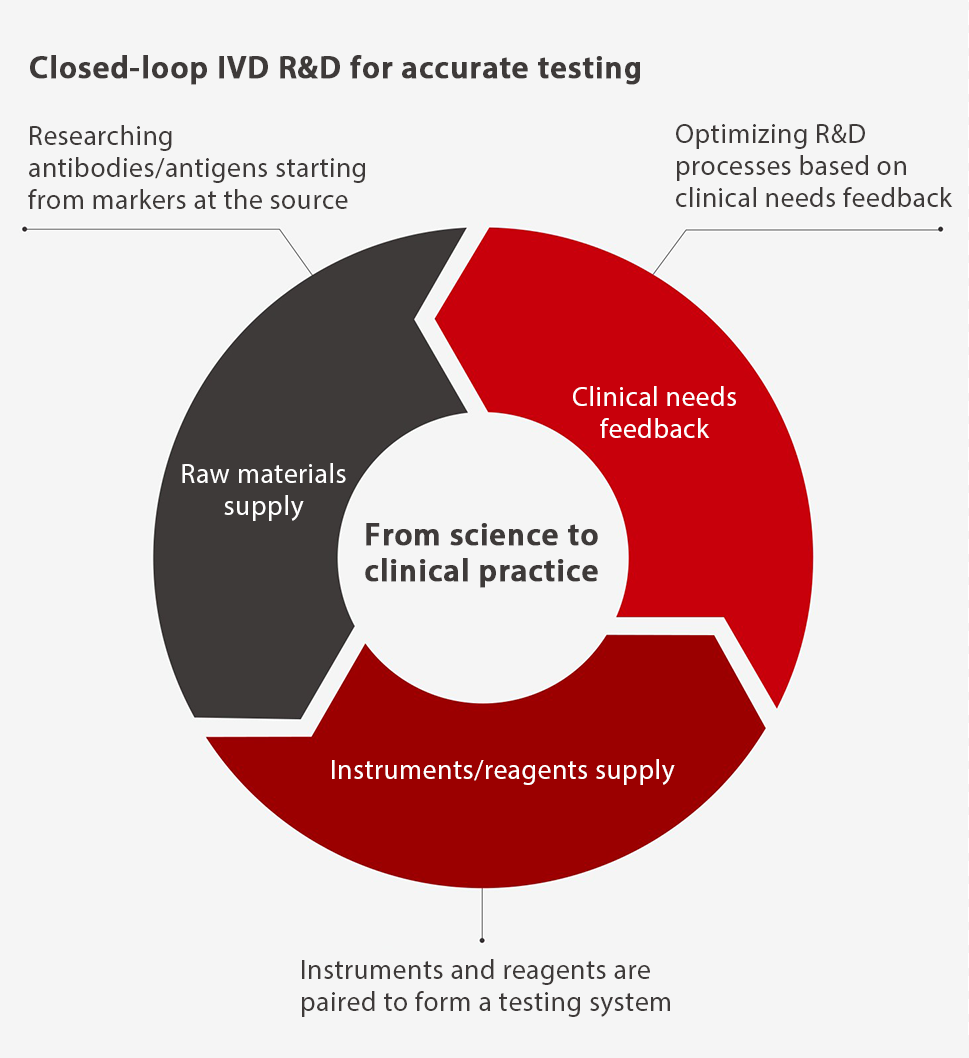

From "numbers" to "value" From science to

clinical practice

View from the bridge

IVD is a bridge that leads science to clinical practice, that is, the clinical application of experimental science is a "view from this bridge".

In order to innovate on reagents from the source and deliver quality reagents that give accurate test results, Mindray has acquired HyTest to bring together a wider group of scientists to unlock more possibilities with immunodiagnostics.

By building a closed-loop system that encompasses everything from antigen/antibody development through to reagent design to test instrument development and manufacturing, Mindray will orient its entire R&D path toward clinical needs, building a bridge from science to clinical practice.

In delving deep into the microworld to study life sciences, Mindray has been dedicated to innovating technologies and methods to design testing principles, to obtain numbers from testing systems, and to create value from clinical application. The shift from "numbers" to "value" is where the real value of IVD lies and what to view from Mindray's IVD bridge.